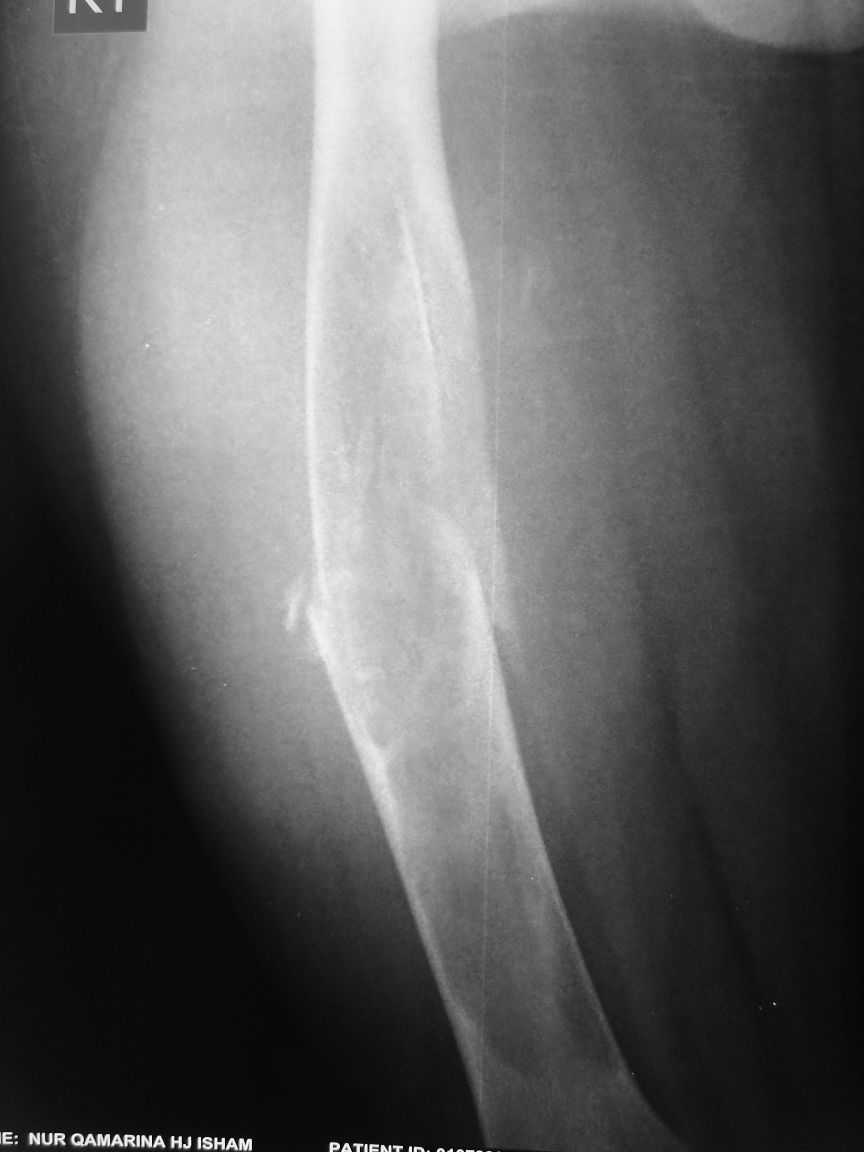

[Ortho] Pathological fracture femur

The attached xrays are of a 13 year old girl, who presented to us

with a history of trivial trauma.  X-rays showed a pathological fracture

right femur through a large radioluscent expansile lesion. All

blood investigations are normal. Clinically no other positive findings.

We assume this to be a case of fibrous dysplasia, and plan to do a

biopsy from the site. Would like your opinion regarding any other

possibility in the diagnosis and treatment options.